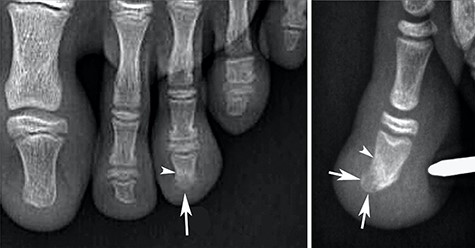

Conventional radiography showed a discrete deformation and irregular density of the phalangeal tuft (Fig. 2). The color Doppler ultrasound showed a hypervascularized pattern of swollen soft tissues on the dorsal aspect of the phalangeal tuft, suggesting a glomus tumor (Fig. 3). A CT scan showed a small lucent bone area within a focal hypertrophy of the phalangeal tuft with adjacent bone sclerosis (Fig. 4). Based on this latest examination, the diagnosis of OO of the distal phalanx was proposed as diagnosis.

Radiographs showing heterogenous density of the distal phalange of the third toe on the anteroposterior view (arrow in A) and a hypertrophy with low density of the dorsal part of this phalangeal tuft on the lateral view (arrows in B). Note also a discrete densification of the adjacent bone (arrowheads).